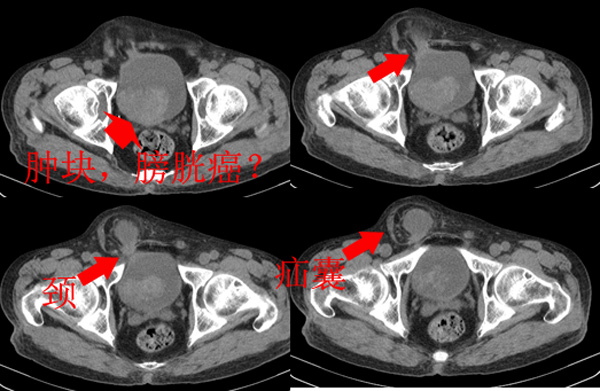

m79y自述30年前做过疝手术,20年前间断出现尿血,每次经抗炎治疗后即好转,近一月来又出现尿血但抗炎后仍尿血.现做双肾+盆腔ct:

该病人年龄过大故放弃了增强.ct做完后本人检查病人发现病人耻骨联合上稍偏右见一突出的包块影,质地柔软,平卧位手压后可以回缩.站立位突出明显!

考虑膀胱ca,右侧腹股沟斜疝。

1、膀胱内占位性病变,膀胱癌可能性大。

2、腹部沟斜疝。

膀胱三角区右侧可见较大软组织肿块,分叶状,内可见更低密度区,ct做完后本人检查病人发现病人耻骨联合上稍偏右见一突出的包块影,质地柔软,平卧位手压后可以回缩.站立位突出明显!考虑腹股沟斜疝,疝内容物为膀胱.膀胱内肿物考虑1炎性赘生物2平滑肌肉瘤(有多年血尿史,本次加重且抗炎不好转)3膀胱癌

1.膀胱内软组织肿快,有点状钙化,前列腺不大.膀胱癌.

2.右侧腹股沟斜疝。

盆腔超级经典病例--膀胱癌+膀胱疝出引起的右侧腹股沟斜疝膀胱疝,果然名不虚传!谢谢楼主!   “m79y自述30年前做过疝手术,20年前间断出现尿血,每次经抗炎治疗后即好转”,这是因为膀胱的疝入甚至短暂或部分嵌顿以及由此引起的炎症所造成,当然抗炎治疗后好转;“近一月来又出现尿血但抗炎后仍尿血”,这就是膀胱癌在作怪了,呵呵。

首先,膀胱癌可以肯定,右侧斜疝内内容物是什么?好象和膀胱相连,我看象是膀胱憩室,患者多年血尿病史也支持.当然要是增强了就可以确诊.

1、右侧腹股沟斜疝,疝内容物为膀胱;2、膀胱右后壁肿块,考虑膀胱癌